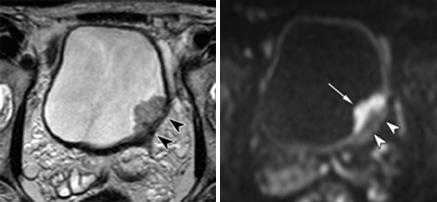

Неинвазивная уротериальная карцинома.

а) Т2-аксиальное изображение б) DW-аксиаальная плоскость

Мужчина, 49 лет, уротелиальная карцинома.

а) Т2-взвешенное изображение показывает опухоль с тканевой интенсивностью МР-сигнала на заднее-левой стенке мочевого пузыря. При этом видно легкое повышение интенсивности МР-сигнала от гипоинтенсивной в норме стенки пузыря (стрелки). (б Диффузинно-взвешенное изобрежение показывает опухоль (тонка стрелка) и ее распространение в подслизистый слой (головки стрелок), без признаков инвазии в мышечный слой.

Инвазивная уротелиальная карцинома.

а)Т2-tra б) Т1-sag в)Т2-диффузия (DW)

Мужчина, 72 года. В заднее-левых отделах мочевого пузыря визуализирвется объемное образование (уротелиальная карцинома), стадия 3b.

(а) Аксиальное T2-взвешенное изображение показывает больших размеров опухоль с инвазией мышечной стенки и развитием гидроуретера (стрелка). Видна инвазия мышечного слоя, но достовено судисть о паравезикальном распространении невозможно.

(б) Динамическое контрастирование на скане, проходящем перпендикулярно к основанию опухоли выявляет тотальное поражение стенки пузыря, нечеткость заднего контура опухоли.

(в) Поперечное диффузионно-взвешенное изображение демонстрирует большую опухоль с признаками трансмурального роста и инвазии в паравезикальную клетчатку (стрелка).